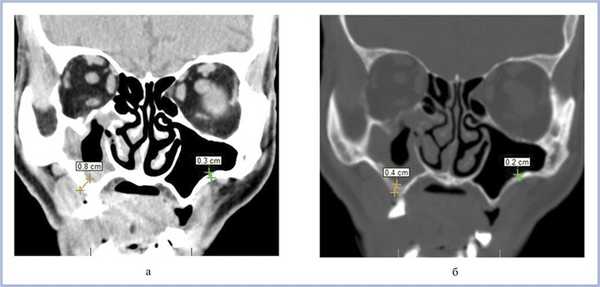

Пломбировочный материал был обнаружен у 38 (22,8%) пациентов (рис. 2). Из них у 34 (20,4%) больных в подслизистом слое нижней стенки синуса, у 4 (2,4%) — в верхнем отделе у медиальной стенки синуса (рис. 3). У 8 (4,8%) пациентов диагностированы ошибки стоматологической имплантации: верхушка импланта была погружена в полость синуса, что стало причиной развития хронического одонтогенного верхнечелюстного синусита, а также осложнений в виде хронического полисинусита (n=4; 2,4%).

Рис. 2. МСКТ. Коронарная (а) и сагиттальная (б) реконструкции правого верхнечелюстного синуса пациента К., 29 лет. Диагноз: правосторонний одонтогенный хронический верхнечелюстной синусит. Корни зубов 1.6, 1.7 и 1.8 погружены в полость верхнечелюстного синуса. Состояние после эндодонтического лечения зубов 1.6 и 1.7, с выведением пломбировочного материала за верхушку небного корня 1.7. В области корней зубов 1.6 и 1.7 отмечается разрежение костной ткани с нечеткими неровными контурами (рентгенологические признаки гранулирующего периодонтита). В нижнем отделе синуса определяется пристеночное мягкотканное образование с полицикличным контуром, костные стенки синуса в данной области не прослеживаются.

Воспалительные изменения слизистой оболочки верхнечелюстной пазухи, существующие в течение длительного времени, вовлекают в процесс костную стенку. На компьютерных томограммах отмечается утолщение костной стенки в костном режиме и появление «оптического эффекта» — уплотнение стенки в 1,5—3 раза за счет отека надкостницы — при просмотре в мягкотканом режиме (рис. 1, а, б) [9]. При одностороннем процессе, характерном для одонтогенного поражения, на контралатеральной интактной стороне такого эффекта не определяется.

Рис. 1. Рентгеновская компьютерная томограмма околоносовых пазух. Коронарная проекция: мягкотканное окно (а) и костное окно (б).

В костном режиме программы просмотра изображений утолщение костных стенок верхнечелюстной пазухи определялось в 21% случаев (рис. 2, 3), что указывает на хронический характер воспаления. «Оптический эффект» в мягкотканном режиме программы просмотра диагностических изображений определялся у 30,7% больных, что указывает на вовлечение надкостницы.